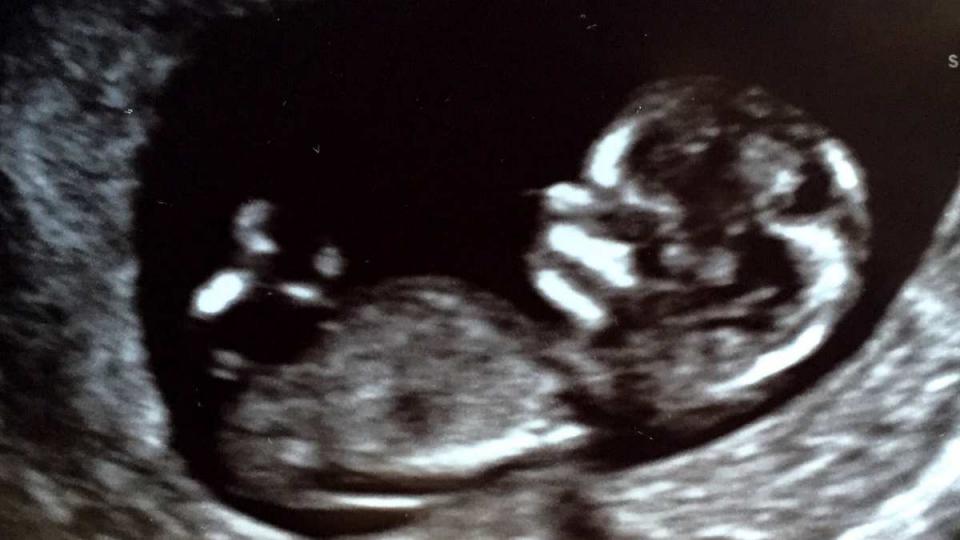

Η Κάθριν Χέιγκλ είναι έγκυος!

Η ηθοποιός Κάθριν Χέιγκλ, ευρέως γνωστή από τον ρόλο της στην αμερικάνικη σειρά Grey's Anatomy, είναι έγκυος για πρώτη φορά!

Στο προσωπικό της blog, η ίδια είπε πως η εγκυμοσύνη της ήρθε τελείως ξαφνικα "Όπως με έιχε ενημερώσει ο γυναικολόγος μου, είμαι μεγάλη σε ηλικία πια για να μείνω έγκυος, οπότε δεν πιστεύαμε πως μια εγκυμοσύνη ήταν στα χαρτιά μας."

Το μωρό, το οποίο είναι αγοράκι, είναι το πρώτο βιολογικό παιδί του ζευγαριού. Η ηθοποιός με τον σύζυγό της, τραγουδιστή Τζος Κέλλυ, έχουν ήδη δύο κόρες που έχουν υιοθετήσει, οι οποίες σύμφωνα με την μητέρα τους είναι κατενθουσιασμένες με το γεγονός!